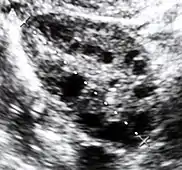

Diagnostic method | Blood tests, ultrasound[1][4] |

Polycystic ovary syndrome accounts for about 70% of hyperandrogenism cases.[1] Other causes include adrenal hyperplasia, insulin resistance, hyperprolactinemia, Cushing's disease, certain types of cancers, and certain medications.[4][1][3] Diagnosis often involves blood tests for testosterone, 17-hydroxyprogesterone, and prolactin, as well as a pelvic ultrasound.[1][4]